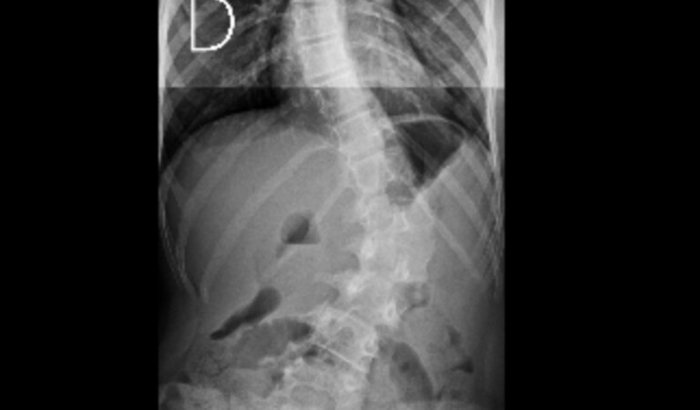

Oii criei essa vaquinha pois minha filha Heloísa foi recentemente diagnosticada com escoliose em graus avançados, precisando urgentemente de tratamento para que uma cirurgia de risco e complexa seja evitada.A Helo tem 13 anos, estuda, vai a igreja e brinca com as amigas. Recentemente recebemos o diagnóstico de escoliose na coluna dela, os graus já são preocupantes. Em uma primeira opinião médica foi recomendado uma cirurgia para a colocada de 26 pinos aos longo da coluna, para então ter uma melhora de 50% do problema. Já em uma segunda opinião, essa de um especialista de São Paulo, foi recomendado o uso de colete para uma porcentagem maior de melhora.